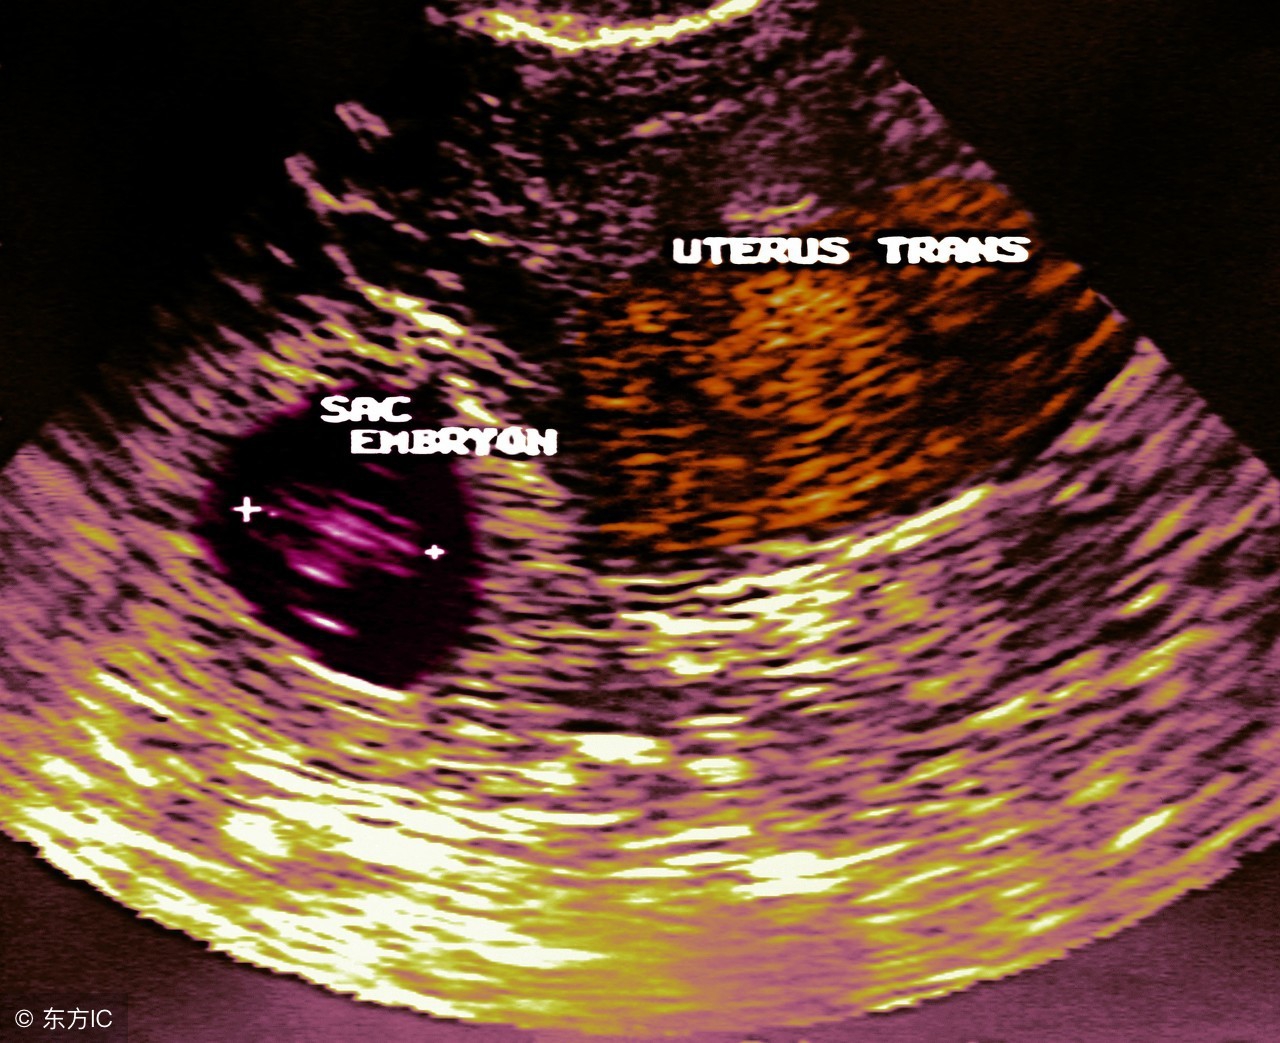

手术后在家休养了半年,小灵又怀孕了,她非常担心,害怕又是宫外孕可怎么办?每天过得提心吊胆,直到发现在宫内,才舒了一口气。

由此可见,宫外孕是一件非常危险的事情,容易造成大出血,流产,引起休克,甚至是危及女性生命。

宫外孕有三大预警信号:短暂停经史或者月经延迟,不规则阴道流血;腹痛;输卵管妊娠流产或破裂所形成的血肿与周围组织器官粘连、包裹形成包块。如果出现这三个警报,一定要注意。